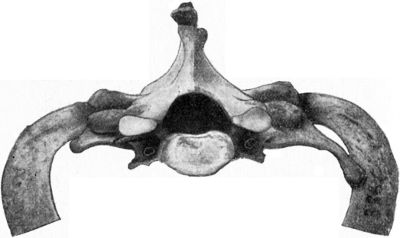

| 209. | Fracture of Odontoid Process of Axis Vertebra | 429 |